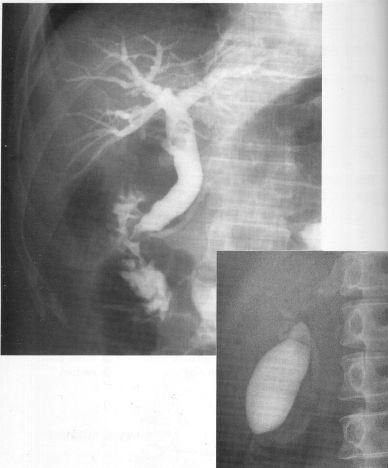

浅ノ川総合病院 放射線部 胆嚢造影・膵管造影

胆嚢造影・膵管造影

浅ノ川総合病院 放射線部 腎盂造影

腎盂造影

浅ノ川総合病院 放射線部 膀胱造影・尿道造影

膀胱造影・尿道造影

胆嚢造影では胆嚢の状態や機能を知ることができます。

膵管造影は総胆管や膵臓の膵管の中に直接造影剤を注入し、胆管、膵臓の状態を調べたり胆石、膵石を除去します。

造影剤を静脈注射し、腎臓から排泄される過程を撮影します。

腎臓の機能や形態、結石などを知ることができます。

尿道からチューブを挿入し、造影剤を注入することにより膀胱や、尿管の状態を調べます。

また直接、尿道から造影剤を注入し尿道の形態を観察することで前立腺の状態を調べます。